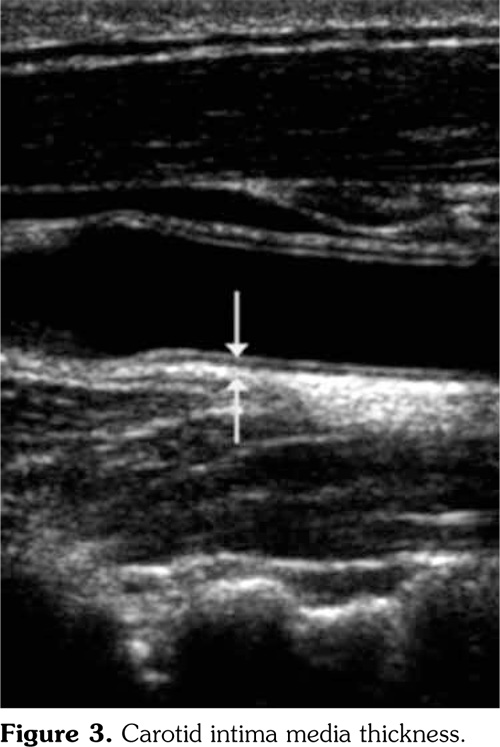

Duplex and color coded Doppler examination of both carotid arteries were performed using an ultrasound machine (Acuson Antares; Siemens, Erlangen, Germany) with a 7.5 MHz transducer. All patients were performed Doppler by B (brightness)-mode grey scale, color, spectral Doppler techniques. We assessed the carotid IMT and any plaques were recorded (Figure 3).